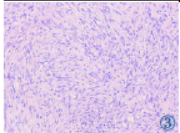

超声引导下经皮肝脏肿瘤穿刺活检光镜见:异型细胞弥漫分布,核大,呈圆形或梭形,包浆透亮,部分胞浆丰富,嗜酸性,可见核分裂象(图3)。免疫组化:CK19(胆管上皮+),CK7(胆管上皮+),Desmin(-),GPC-3(-),Hep(-),INI-1(-),Ki-67(约20%+),PAX-8(-),S-100(-),SALL-4(少量+),SYN(少量+),Vimentin(+),CK(核旁点状+),EMA(少量+),NSE(-),CD99(部分+);特殊染色:PAS(+)。结合免疫组化及特殊染色结果,符合肝脏恶性横纹肌样瘤(Rhabdoid tumor,RT)。

图1 肝脏横纹肌样瘤CT 图。图1a:CT 平扫示肝左叶内侧段见一巨大稍低密度肿块;图1b:增强扫描动脉期示肿块呈不均质轻度强化;图1c,1d:增强扫描门脉期示肝内血管受压推移、下腔静脉受压。图2 肝脏横纹肌样瘤MRI 图。图2a:T1WI 示肿块整体呈低信号;图2b,2c:T2WI 压脂示肿块整体呈高信号,夹杂高信号和低信号;图2d:T2WI 压脂示胆囊向左移位。图3 肝脏横纹肌样瘤病理图。光镜见异型细胞弥漫分布,核大,呈圆形或梭形,包浆透亮,部分胞浆丰富,嗜酸性,可见核分裂象(HE)。

EERT 趋向原发于中轴的深部软组织,如头颈部、纵隔,也可发生于盆腔以及肝脏等部位,瘤体巨大,长径多大于5 cm 甚至达8 cm,较少见小于3 cm 者,临床表现无特异性,主要表现为体表肿块。病理上,肿瘤细胞弥漫成片,呈多形性,大部分RT 病理性核分裂象易见,Ki-67 增殖指数较高,肿瘤细胞具有多种免疫表型特性,EMA、SYN、Vimentin、CD99 等可呈阳性,由于编码INI-1 蛋白的SMARCB1(又称hSNF5/INI-1)基因发生缺失,促进肿瘤形成,所以INI-1 蛋白免疫组化检测可作为诊断RT 的金标准,本病例病理表现均支持RT 诊断。